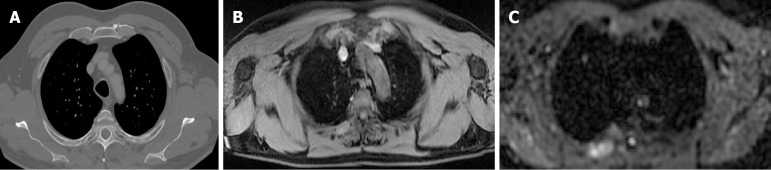

Results: Sixteen studies involving over 700 patients met the inclusion criteria. WB-MRI showed high sensitivity (73%-90%) and specificity (up to 98%) in detecting metastases, particularly in bone, liver and soft tissue. DWI enhanced lesion detection, and WB-MRI often influenced clinical management decisions. However, CT outperformed WB-MRI in identifying small pulmonary nodules. AI-assisted analysis and contrast-enhanced sequences further improved diagnostic confidence.